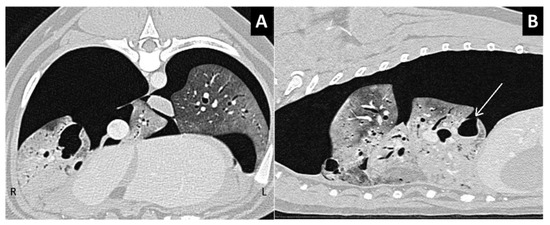

Figure 8.

(A,B) Transverse and right-parasagittal views of the thorax in a patient with subpleural lung laceration and massive pneumothorax, with subsequent lung collapse.